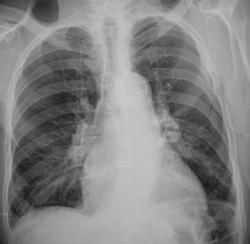

Взяли на контроль после "флюшки".

очень тут хочется томо серединный срез))))) С корешками "поиграться"))).......и аорта тут красивая)))

Похоже возраст, но есть группа кальцинированных узлов, т.е. R+ пока.

Нет, не как рентген- положительный. По картинке то - да, раньше, по всей видимости болел, болел  без дураков. Но в туб кабинете его не помнят.

Да, кальцификатов до фига.

А корни на саркоидозные не похожи?

Ну вроде ж "скорлупа". Или нет?

Не знаю, но в лекции у меня "скорлупа ореха" написана!

При силикозе тоже скорлупа...

Мне сдается все это - "дела давно минувших дней"))))

Это другой разговор...там л\узлы "посвежее"...только  нет полной уверенности, что именно они....

Как то теряюсь между центральным новообразованием и просто - артериальной гипертензией...если бы не ТАКИЕ л\узлы слева, "смазывающие" левый корень...

думаю,что лимфоаденопатия справа присутствует,легочная гипертензия тоже есть-никуда не денешься. Отдать клиницистам с динамическим контролем. Вам, Валентин Львович,за томо спасибо)))))

Может это перенесенный в далеком детстве бронхоаденит? Ну тогда дела давно минувших дней ,и пациента отпустим... Впрочем наверное не отпустим. В верхних отделах средостения справа нечто, похожее на онкологию

Лимфоузлы корня правого лёгкого калцинированы не скорлупообразно. Типичный случай естественной туберкулёзной прививки.